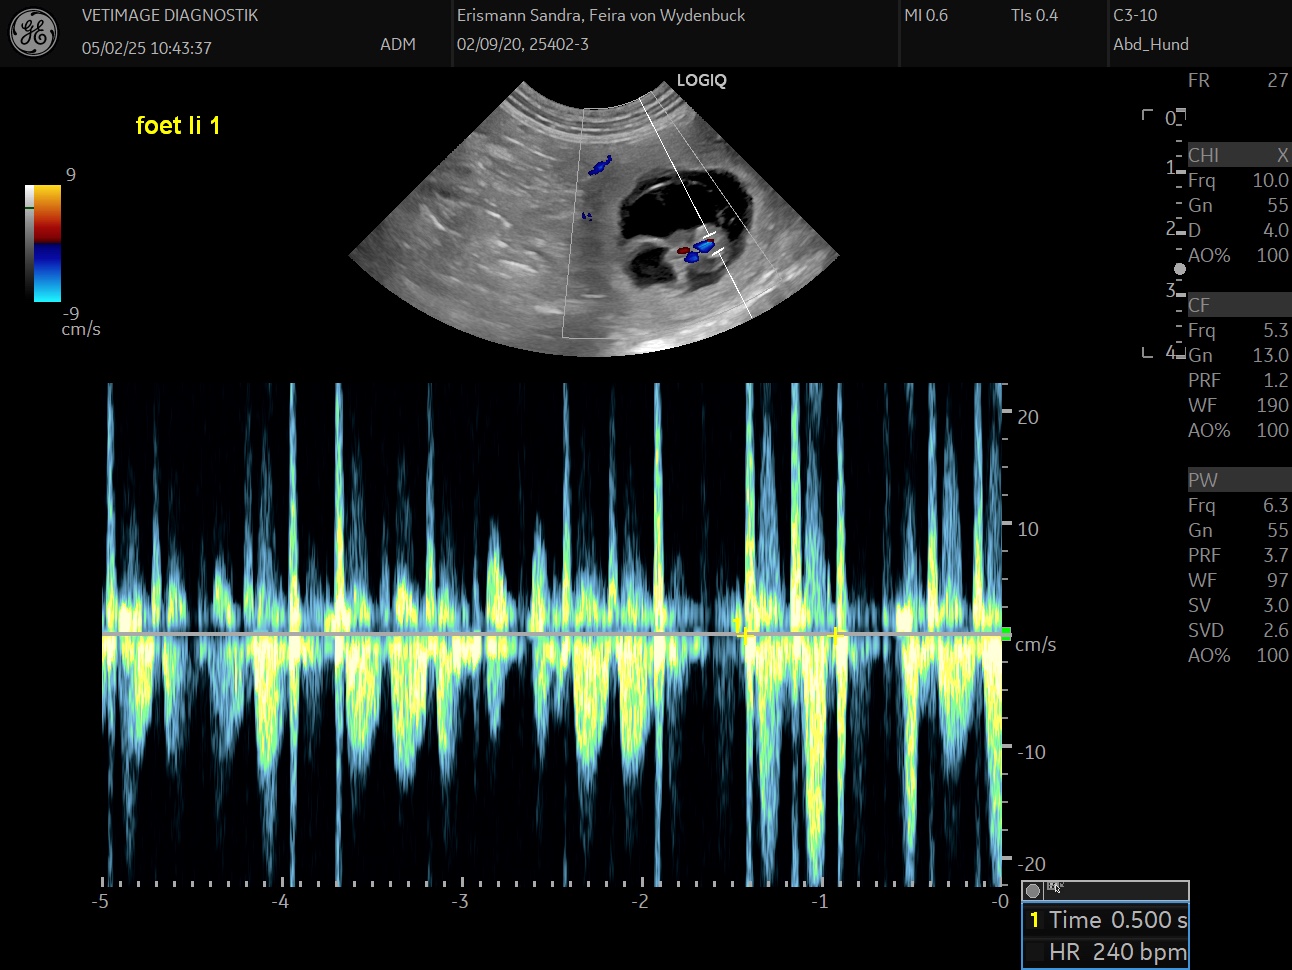

Unsere Feira hatte den Ultraschall, und sie trägt kleine Föten von ca. 1.2 cm im Bauch mit 230-240 Herzschlägen pro Minute.